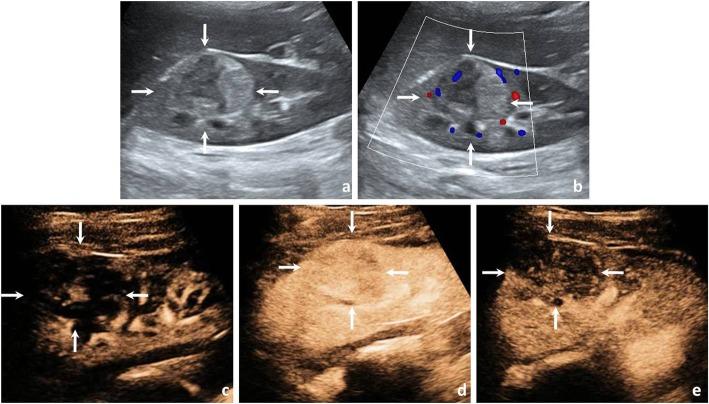

Contrast-enhanced ultrasound findings of adult renal cell carcinoma associated with Xp11.2 translocation/TFE3 gene fusion: comparison with clear cell renal cell carcinoma and papillary renal cell carcinoma.

In total, 110 patients (110 renal masses) who underwent CEUS examinations were enrolled in this study. The cases included 18 Xp11.2/TFE3 RCCs, 60 ccRCCs and 32 pRCCs. All masses were confirmed by operative pathology. The CEUS imaging data of these patients were retrospectively analysed by two readers. The conventional US and CEUS features of Xp11.2/TFE3 RCC were compared with those of ccRCC and pRCC.

The age of the patients with Xp11.2/TFE3 RCC ranged from 20 to 68 years, with a mean age of 38.3 ± 16.3 years and a slight female predominance. The weighted kappa value that interprets the concordance between the interobserver agreement of the US and CEUS features ranged from 0.61 to 0.89. On conventional US and CEUS imaging of Xp11.2/TFE3 RCCs, the tumours were hypoechoic (6/18, 33.3%), isoechoic (8/18, 44.4%), and hyperechoic (4/18, 22.2%). The cystic component was present in 5 cases (27.8%), calcification was present in 9 cases (50.0%), and colour flow signal was present in 7 cases (38.9%). Most cases showed simultaneous wash-in (11/18, 61.1%); the peak enhancement showed hypoenhancement (6/18, 33.3%), isoenhancement (10/18, 55.6%), and hyperenhancement (2/18, 11.1%); most cases exhibited heterogeneous enhancement (12/18, 66.7%) and fast- or simultaneous-out (16/18, 88.9%); and a pseudocapsule was present in 6 cases (33.3%). In the multivariate logistic regression analysis, calcification and lower peak enhancement were more likely to be present in Xp11.2/TFE3 RCC than in ccRCC (P < 0.05), and younger age and relatively high peak enhancement were more likely to be present in Xp11.2/TFE3 RCC than in pRCC (P < 0.05). The calcification combined peak enhancement model differentiated Xp11.2/TFE3 RCC from ccRCC, and the age combined peak enhancement model differentiated Xp11.2/TFE3 RCC from pRCC with an AUC, a sensitivity and a specificity of 0.896, 94.4% and 73.3% and 0.786, 50.0% and 100.0%, respectively.